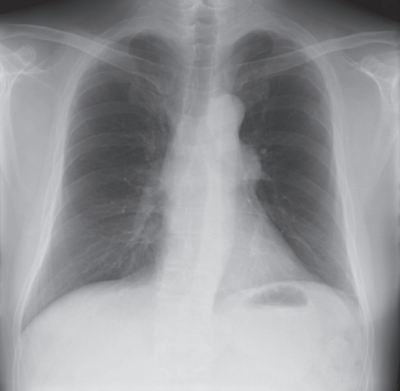

血液所見:赤血球 410 万、Hb 13.0 g/dL、Ht 40 %, 白血球 7,300、血小板 15 万。血液生化学所見:総蛋白6.5 g/dL、 アルブミン 4.5 g/dL、 総ビリルビン 0.6 mg/dL、 直接ビリルビン0.2 mg/dL、AST 20 U/L、ALT 25 U/L、LD 185 U/L(基準 120~245)、ALP 110 U/L(基準 38~113)、 尿素窒素 11 mg/dL、 クレアチニン 0.4 mg/dL、Na 140 mEq/L、K 4.0 mEq/L、Cl 101 mEq/L。CRP 2.0 mg/dL。 術前後の胸部エックス線写真を別に示す。